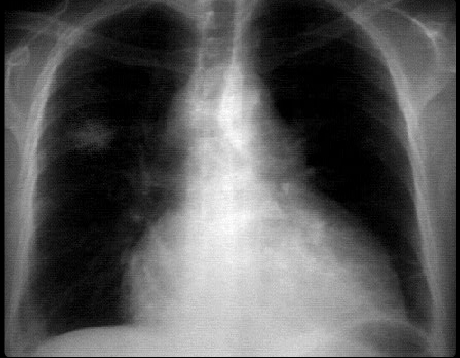

This chest X ray demonstrates a lung mass and pericardial effusion.

The PA view demonstrates a

non-calcified mass in the peripheral portion of the right upper lobe.

The

cardiopericardial silhouette is enlarged. Whether this is a pericardial effusion and/or cardiac enlargement would require additional imaging studies.

This

left hilum is also abnormal from either a mediastinal mass or an enlarged pulmonary artery. With the lung mass, the former is more likely.